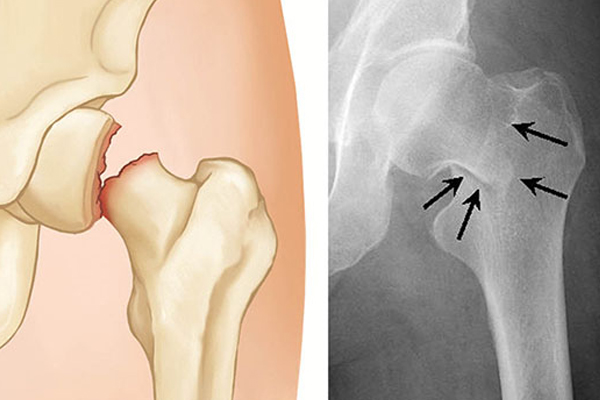

Hip Treatments

Hip Fractures